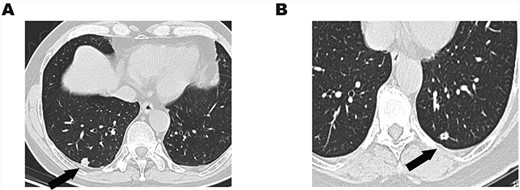

A 58-year-old man was admitted to our hospital due to abnormal chest shadow without any symptoms. Chest computed tomography (CT) revealed an 11-mm peripheral nodule in the right S10 segment (Fig. 1A). He received video-assisted thoracoscopic surgery (VATS), and wedge resection was carried out. The intraoperative frozen examination indicated papillary carcinoma and was unable to distinguish benignity from malignancy. Afterward, a right lower lobectomy was performed.

(A) Chest CT showed an 11-mm solitary nodule with central cavity in the right S10 segment. (B) An 8.5-mm solitary nodule with central cavity in the left S10 segment.